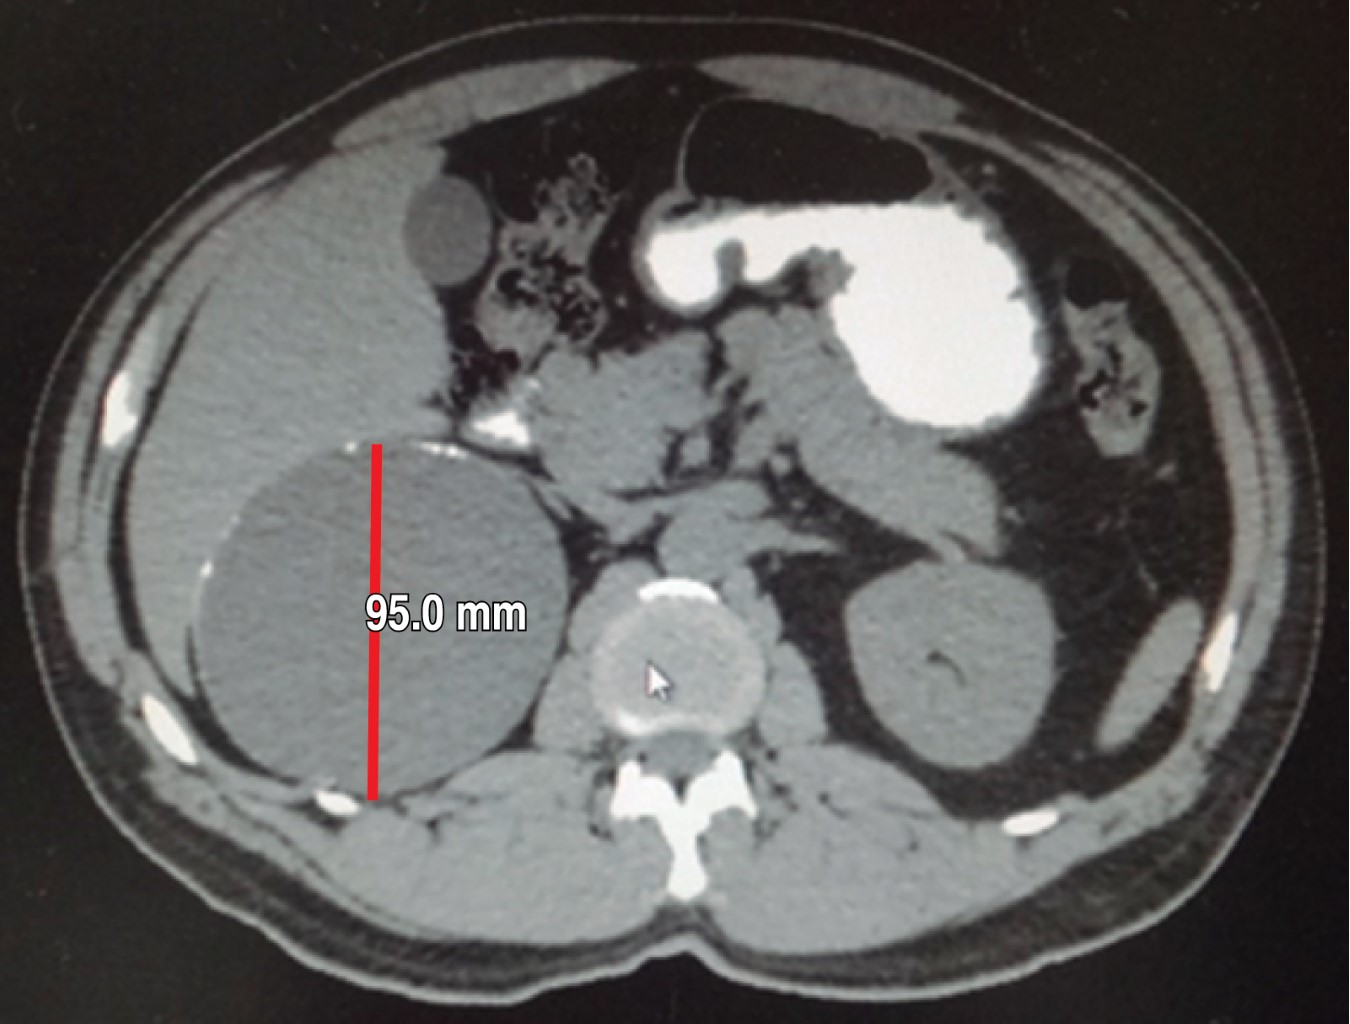

In May 2018 he had normal cytology blood cell counts, liver and renal function tests, and coagulation parameters. No cortisol, aldosterone, urinary catecholamine or metanephrine measurements were done. An abdominal CT scan performed in May reports a right adrenal gland hypodense image with a maximum diameter of 101 mm with calcification images inside it that was exerting occupational and compressive effect on surrounding structures (Figures 3, 4, 5 and 6). Once internal medicine service completed his preoperative assessment, an open anterior surgical approach was scheduled. He was given antibiotic prophylaxis with ceftriaxone 2 g in a single dose before a right subcostal incision was made and we proceeded to electrocautery removal of the right adrenal cyst of 10 × 9 cm. Adhesions to the liver were found and a content of approximately 400 ml of hyaline fluid and calcifications of about 20 × 40 mm in its interior were seen. A Penrose drainage of ½" (19 mm) was placed in the subphrenic space due to the suspicion of postoperative hemorrhage.

Figure 3

Figure 4

Figure 5

Figure 6